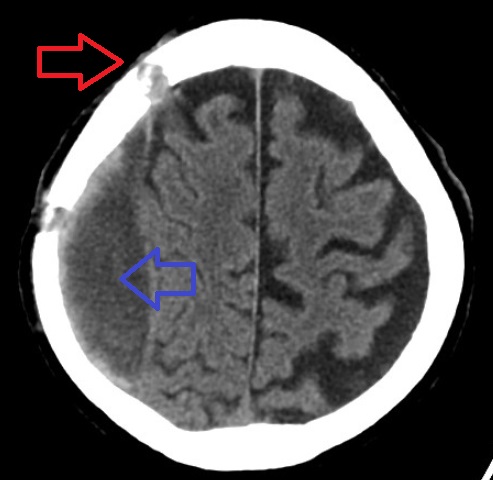

머리 외상 후에는 완전한 신경학적 검사를 포함한 의학적 평가를 받는 것이 중요하다. CT 스캔 또는 MRI 스캔은 일반적으로 심각한 경막하 출혈을 감지한다.

경막하 출혈은 대부분 전두엽과 두정엽의 위쪽과 측면에서 발생한다.[5][6] 또한 후두개와, 대뇌 낫 및 소뇌 천막 근처에서도 발생한다.[5] 두개골의 봉합선을 넘어 확장될 수 없는 경막외 혈종과 달리 경막하 혈종은 두개골 내부를 따라 확장되어 뇌의 곡선을 따라가는 오목한 모양을 생성하며, 소뇌 천막 및 대뇌 낫과 같은 경막 반사에서만 멈춘다.

CT 스캔에서 경막하 혈종은 전형적으로 초승달 모양이며, 두개골에서 멀리 떨어진 오목한 표면을 갖는다. 그러나 출혈 초기 단계에서는 볼록한 모양을 가질 수 있다. 이는 경막하 출혈과 경막외 출혈을 구별하는 데 어려움을 야기할 수 있다. 경막하 출혈의 더 신뢰할 수 있는 지표는 대뇌 반구의 더 큰 부분을 침범한다는 것이다. 경막하 혈액은 소뇌 천막을 따라 층상 밀도로 보일 수도 있다. 이는 공급 시스템이 저압이기 때문에 만성적이고 안정적인 과정일 수 있다. 이러한 경우, 구의 소실 또는 회백질과 백색질 사이의 경계의 내측 변위와 같은 미묘한 출혈 징후가 나타날 수 있다.

신선한 경막하 출혈은 방사선 밀도가 높지만, 세포 요소의 용해로 인해 시간이 지남에 따라 방사선 밀도가 낮아진다. 3~14일 후에는 출혈이 뇌 조직과 등밀도가 되어 놓칠 수 있다.[19] 그 후 뇌 조직보다 저밀도가 된다.[20]